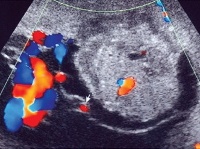

• УЗИ плаценты. На плодовой поверхности плацентарной ткани возле места отхождения пуповины выявляются единичные кистозные или солидные образования с четкими границами (хорошо выраженной капсулой либо псевдокапсулой). Иногда хориоангиомы бывают множественными, размещаются на плодных оболочках, сосудистой ножке, в толще плаценты.

• Допплерография маточно. Плацентарного кровотока. Исследование назначают для определения степени васкуляризации и моделирования структуры сосудистого русла хориоангиомы. С его помощью можно обнаружить связь кровоснабжения опухоли с сосудами пуповины. Для большей информативности метод дополняют цветовым допплеровским картированием.